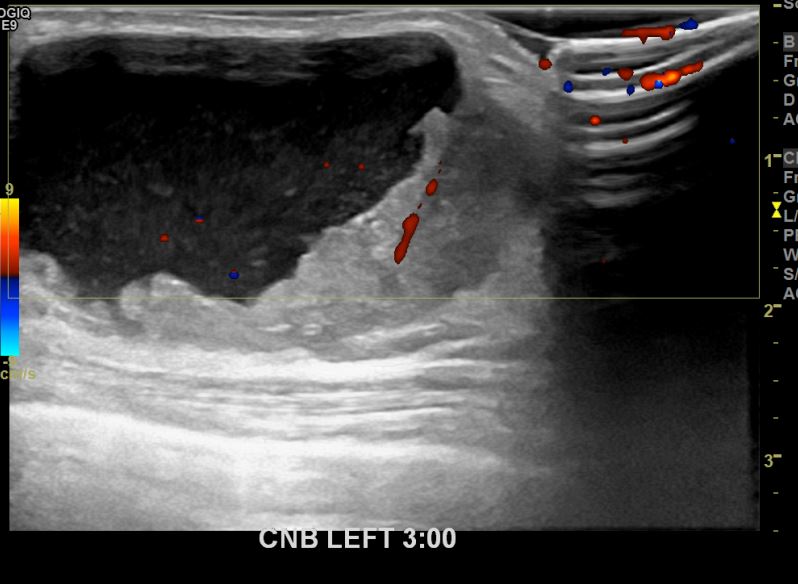

아산유외과개원후 665번째유방암진단

상기환자 외부검사상 이상소견으로 내원하신 80대여성으로 좌측에 의심스러운혹 조직검사시행해 유방암 진단되었습니다